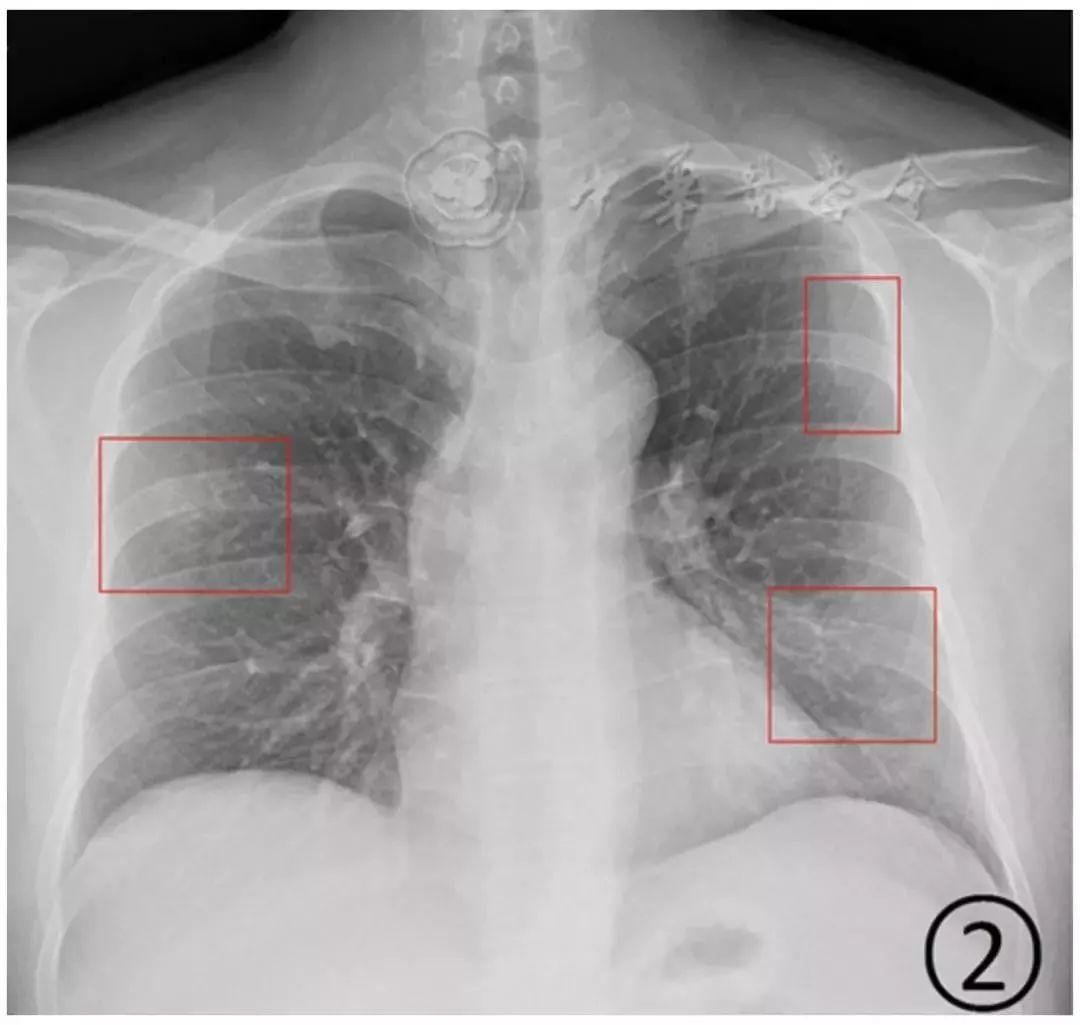

图2 男,43岁,新型冠状病毒感染的肺炎。胸部平片显示右中肺野和左肺上、下肺野散在斑片状阴影,边缘不清

在新型冠状病毒感染的肺炎,病变早期胸部平片检查多无异常发现。核酸检测阳性的普通型患者多表现为两肺中外带和胸膜下的局限性斑片状或多发节段性片状阴影为主(图2)。